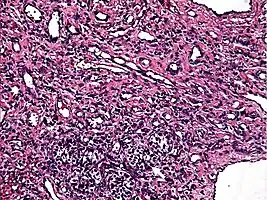

Low power photomicrograph of an endovascular papillary angioendothelioma showing papillae with hyalinized cores

High power view showing a vascular tumor with cuboidal endothelium lining the vessels. Few entrapped seminiferous tubules are also noted (arrow).

Characteristic budding, hobnail-like endothelial cells visible.